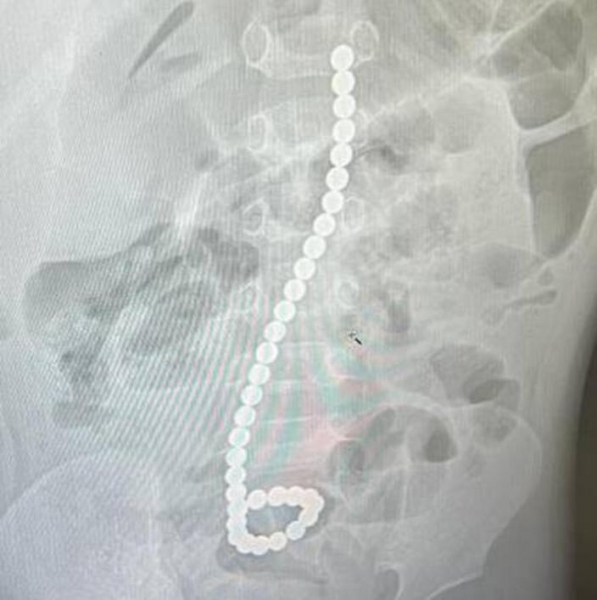

В Московской области врачи спасли полуторагодовалого ребенка, который проглотил 34 магнита. Об этом сообщили в пресс-службе регионального минздрава.

Малыша привезли в Раменскую больницу в тяжелом состоянии. Выяснилось, что дома, когда взрослые отвлеклись, он успел проглотить 34 магнита.

Фото: © Министерство здравоохранения Московской области

«После проведения обзорной рентгенографии органов брюшной полости специалисты обнаружили, что ребенок успел проглотить 34 магнита. Операция была выполнена в экстренном порядке», – сообщили в ведомстве.

В минздраве добавили, что операция прошла успешно. Ребенок чувствует себя хорошо, поэтому его выписали из больницы.